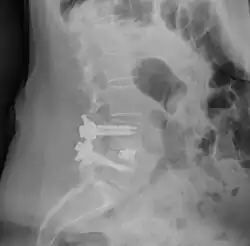

Herniated disc pressing on spinal nerves.

Spinal fusion can be used to treat a variety of conditions affecting any level of the spine—lumbar, cervical and thoracic. In general, spinal fusion is performed to decompress and stabilize the spine.[4] The greatest benefit appears to be in spondylolisthesis, while evidence is weaker for spinal stenosis.[5]

The most common cause of pressure on the spinal cord/nerves is degenerative disc disease.[6] Other common causes include disc herniation, spinal stenosis, trauma, and spinal tumors.[4] Spinal stenosis results from bony growths (osteophytes) or thickened ligaments that cause narrowing of the spinal canal over time.[4] This causes leg pain with increased activity, a condition called neurogenic claudication.[4] Pressure on the nerves as they exit the spinal cord (radiculopathy) causes pain in the area where the nerves originated (leg for lumbar pathology, arm for cervical pathology).[4] In severe cases, this pressure can cause neurologic deficits, like numbness, tingling, bowel/bladder dysfunction, and paralysis.[4]